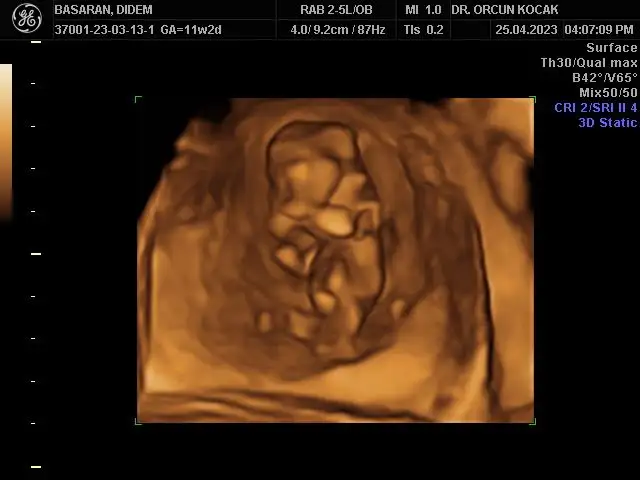

Merhabalar bende 11+5 im tahminlerinizi çok merak ediyorum kızlar sizce ne olabilirRamzi de nub’ u da erkek görünüyor canım

Bu ultrason görüntüsü mü yoksa alttan mı? Ultrasonsa benimkiyle aynı da kafatası bile. Ay ultrason yazmışsın zaten ya farketmedim. Sağlıkla kucağına al inşallah evinize neşe getirsin.Ultrason görüntüsü bugünün böyleydiben erkek hissediyordum bu sefer bulantım filan olunca ama değilmiş hiç teorilere bakmadım açıkçası o yüzden bilmiyorum